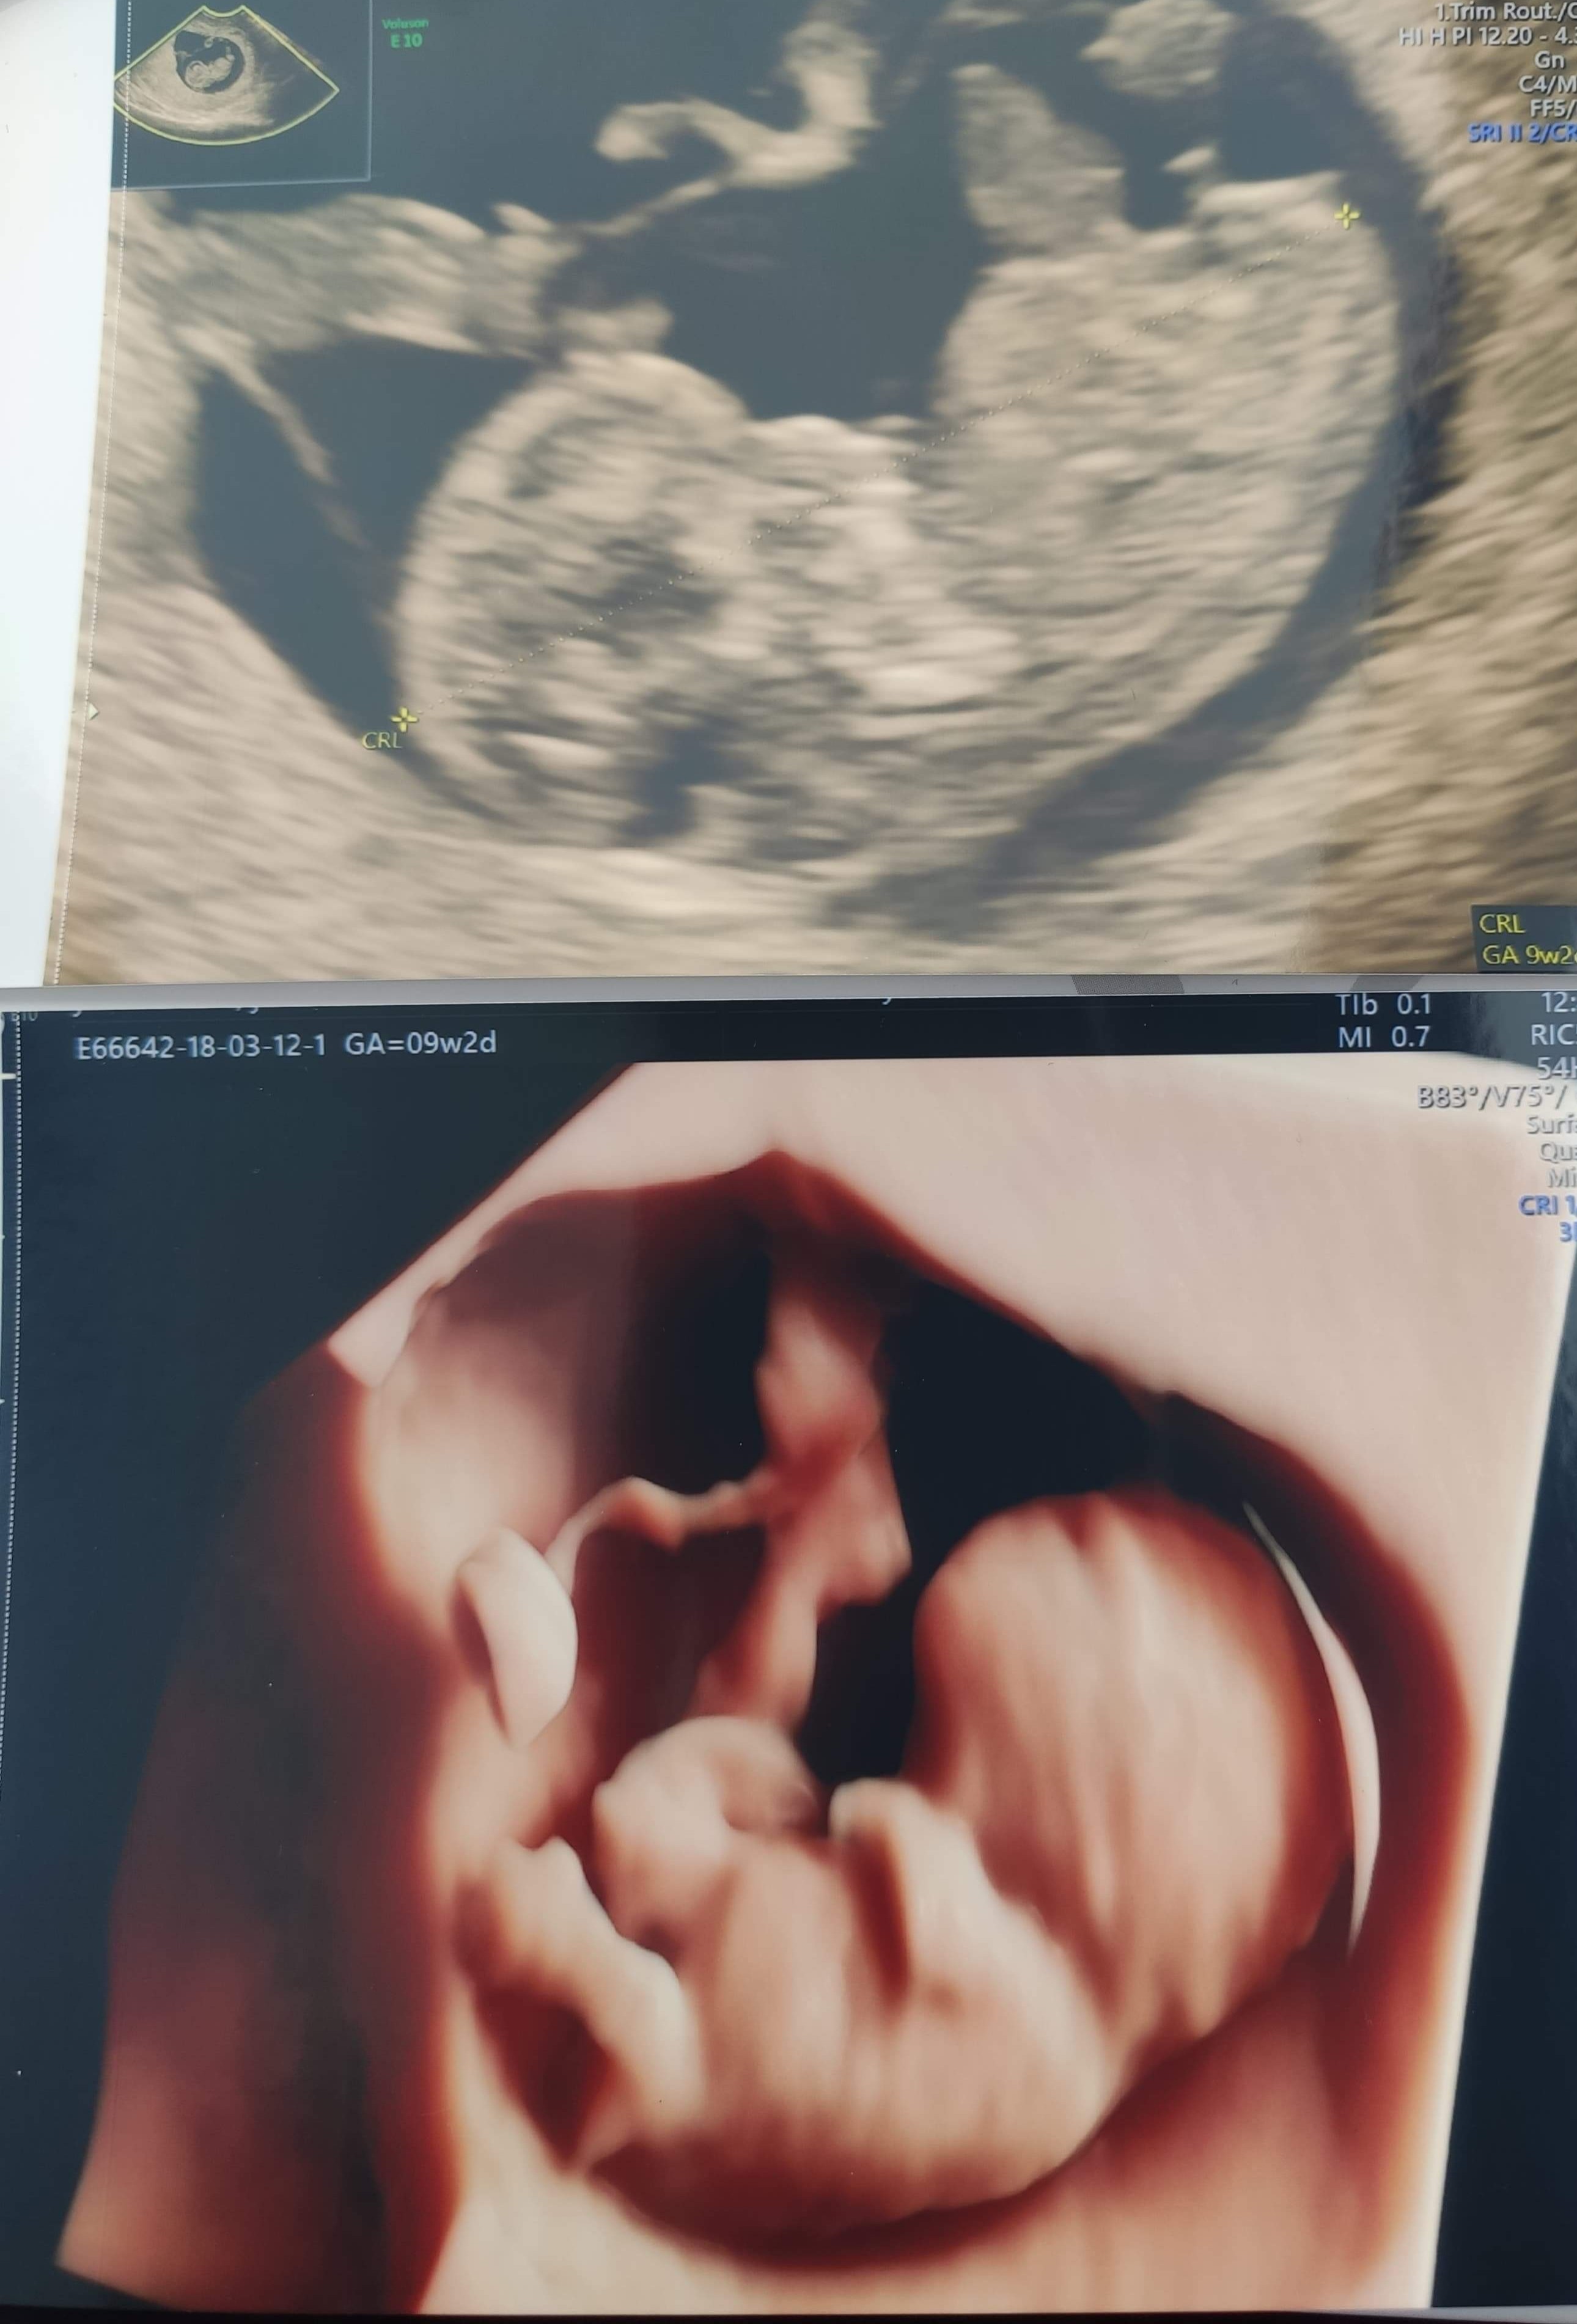

Czekam na kolejne USG, które dopiero za 2 tygodnie

już bym chciała dzidziusia znów zobaczyć, a tu tyle czekania...